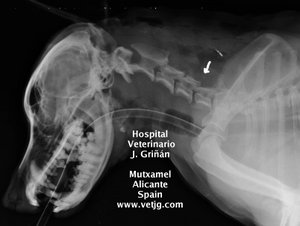

radiografía: imagen del postoperatorio, indicando la zona abordada |